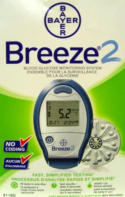

- Blood Test Kits

- Blood Test Kits

- Blood Test Kits